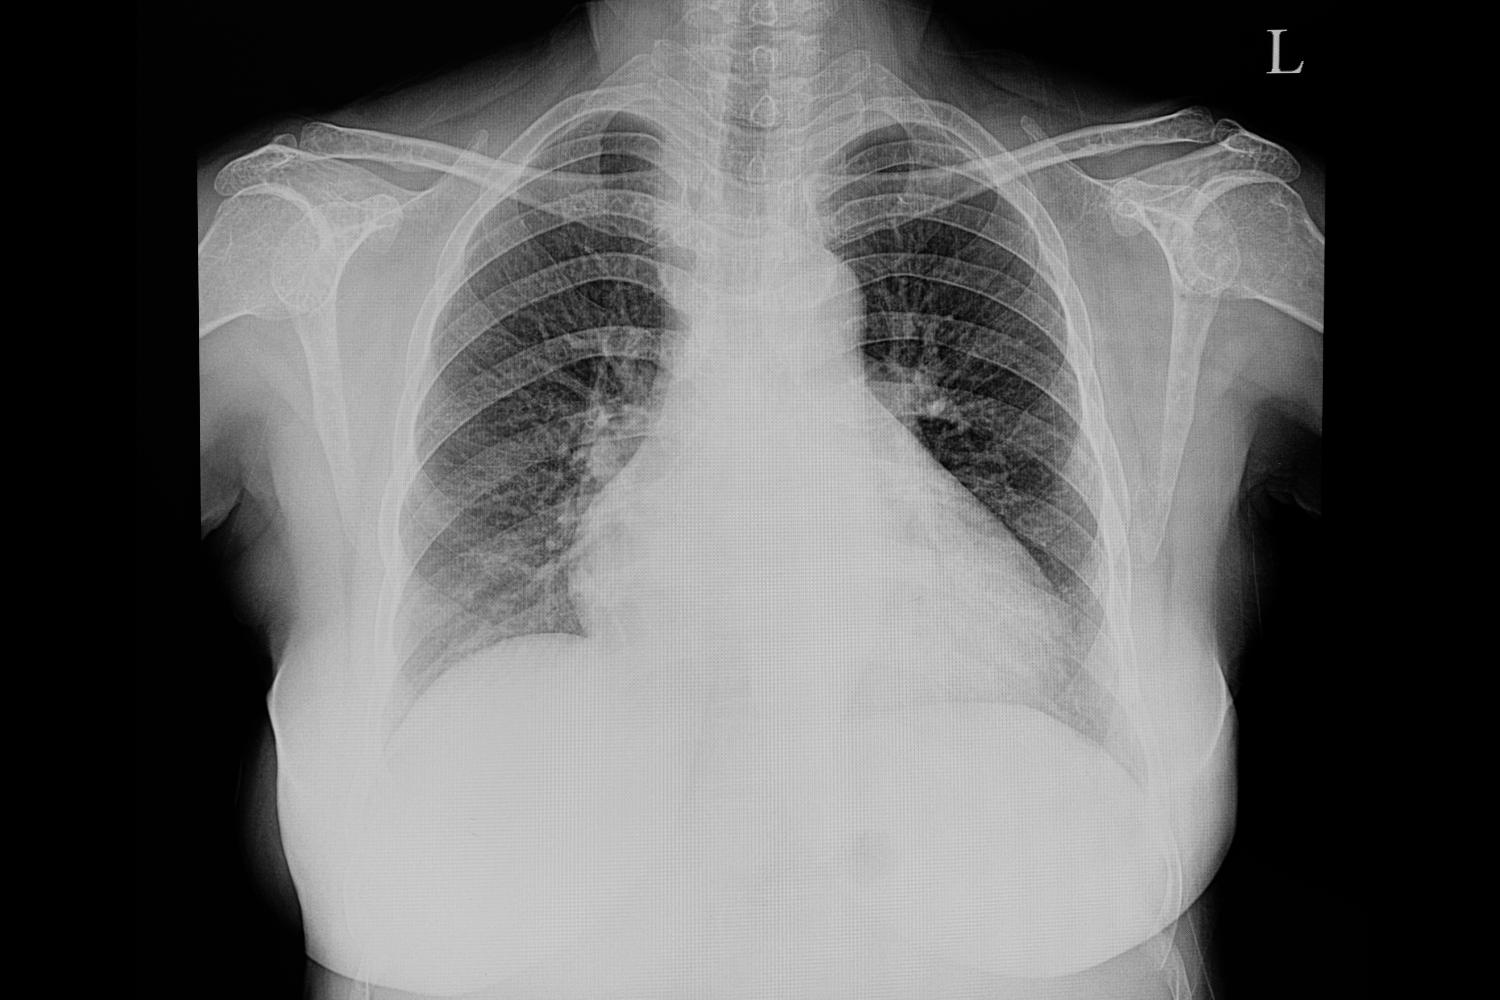

Il termine cardiomegalia indica l’ingrossamento del cuore, evidente se il paziente viene sottoposto a diagnostica per immagini (ad esempio raggi X), che può presentarsi come conseguenza di

La patologia può essere diagnosticata tramite tecniche di imaging, che devono essere seguite da esami specifici volti ad individuare la causa primaria della cardiomegalia, evidenziando od escludendo la presenza di altre malattie responsabili.

- Esami di diagnostica per immagini per evidenziare la forma e le dimensioni del cuore, quali: